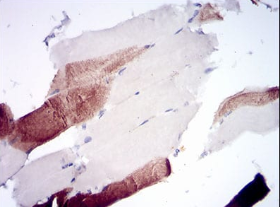

IHC    1/200 - 1/1000